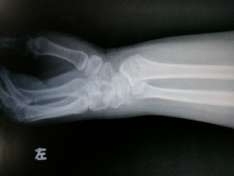

桡骨远端骨折整复前

一、中医手法整复